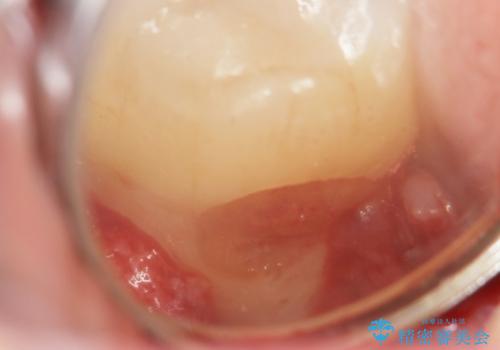

精査したところ、横向きに生えた親知らずのせいで隣の歯(右下7)が虫歯になっていました。

親知らずを抜歯して隣の歯のう蝕を除去し、歯肉の治癒をしっかり待ったのち、患者様のご希望によりゴールド(PGA)クラウンによる補綴を行いました。